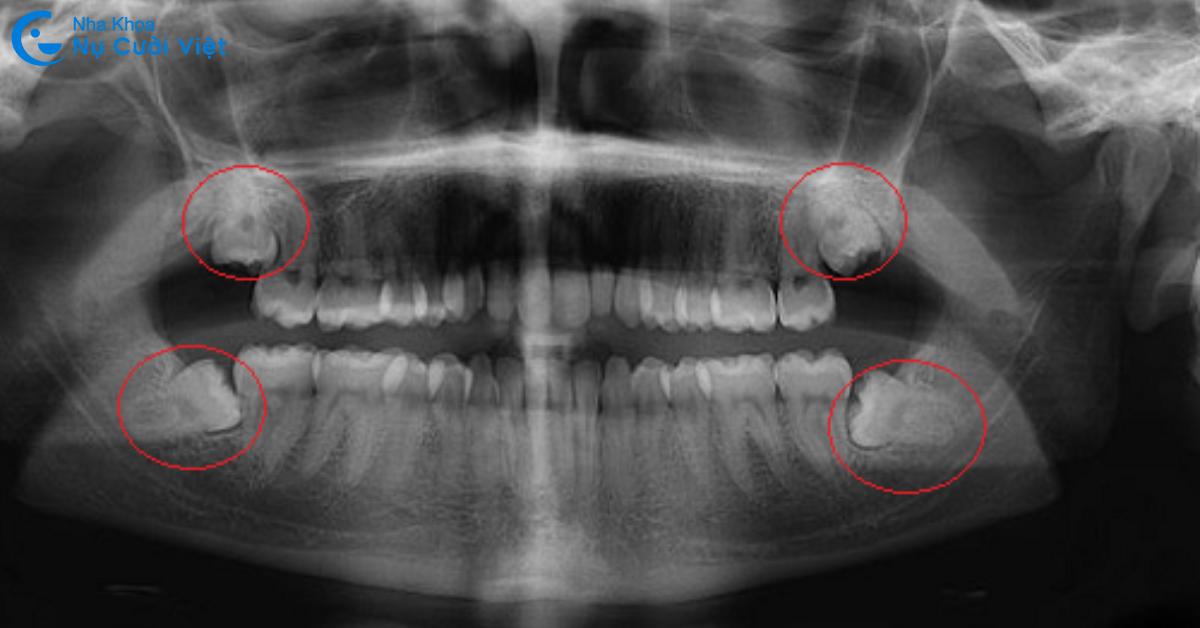

Răng khôn (răng số 8) là các răng hàm xuất hiện cuối cùng khi bạn đến độ tuổi 17 - 25. Chiếc răng này có thể mọc trước, mọc trong hoặc mọc sau quá trình niềng răng. Tùy vào trường hợp răng khôn có ảnh hưởng gì đến phác đồ niềng răng hay không mà bác sĩ có thể chỉ định khác nhau. Cụ thể, dưới đây là những trường hợp cần phải nhổ răng khôn khi niềng răng:

Răng khôn mọc lệch, nằm ngang hoặc đâm vào răng bên cạnh

Nếu răng khôn mọc lệch, hướng vào má hoặc răng số 7, đặc biệt là mọc ngang 90 độ, việc nhổ là cần thiết. Răng khôn trong trường hợp này có thể gây áp lực lên răng kế cận, dẫn đến đau nhức, viêm nướu hoặc sâu răng số 7. Ngoài ra, lực kéo của mắc cài hoặc khay niềng sẽ bị cản trở, khiến hiệu quả điều trị giảm và thời gian niềng kéo dài hơn.

Chụp X quang răng kỹ lưỡng: Bác sĩ sẽ thăm khám kỹ lưỡng, chụp X-quang cẩn thận để làm căn cứ đánh giá cấu trúc và tình trạng răng miệng của khách hàng.